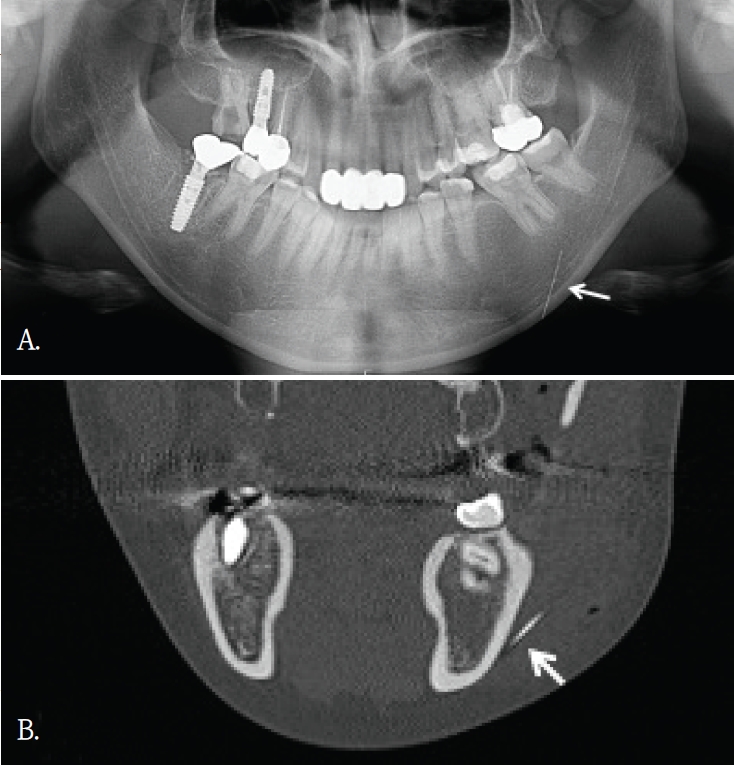

20대 여자환자가 윗 입술의 불편감을 주소로 내원하였다. 파노라마방사선영상에서 관련된 이상소견이나 병변이 관찰되지 않았다(Fig. 1A). 과거병력 청취에서 교통사고로 인한 윗 입술 열상의 봉합 병력이 있었음을 파악한 후, 외상 후 연조직 섬유화로 진단되었다. 1년 후, 이물감을 호소하면서 환자는 재내원하였다. 파노라마방사선영상에서는 여전히 이상소견이 관찰되지 않았기에, 콘빔CT검사를 시행하였다. 윗입술과 상악 전치사이 연조직부위에서 블럭모양의 방사선불투과성 이물질이 발견되었다(Fig. 1B). 이물질 제거를 위한 외과적 수술이 시행되었고, 술 후 해당 이물질은 유리조각임이 확인되었다.

A. Panoramic radiograph shows no definite abnormality in the maxillary anterior region. B. Cross-sectional cone-beam computed tomographic image of the maxillary anterior alveolar region demonstrates a small block-shaped radiopaque foreign body in the labial soft tissue, without intraosseous involvement.

증례 1에서도 초진시 파노라마영상에서는 유리조각을 관찰할 수 없었기에 연조직 병변으로 진단되었으나, 재내원후 촬영된 콘빔CT영상에서 연조직내에 있었던 이물질임으로 확인된 경우이다. 윗입술에 있었던 유리조각이 방사선불투과성 물질이였지만, 상악 전치부와 중첩되어 파노라마방사선영상에서 뚜렷하게 구분되지 않았다.